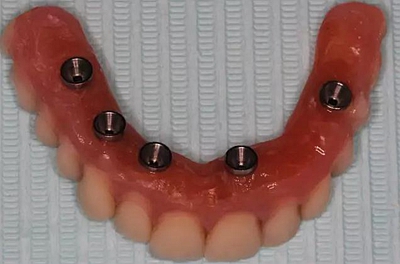

牙列缺失患者由于支持、固位、穩(wěn)定不足導致義齒效果差,如果在牙槽嵴內(nèi)植入種植體,種植體可以根據(jù)種植體數(shù)量不同提供義齒不同程度的固位、穩(wěn)定、支持,獲得不同的修復效果。當單頜牙列缺失患者使用1-2顆植體,植體和覆蓋義齒之間可以靠一些附著體如磁性附著體、桿卡式附著體、球帽式附著體等裝置連接,主要提供固位和穩(wěn)定作用,少量的支持作用,當單頜牙列缺失使用4顆植體時,很大部分支持力可以由植體承擔,當使用4顆以上植體時可完全由種植體提供義齒的支持、固位和穩(wěn)定,甚至制作為不可摘戴的全口固定種植義齒。

1、種植固定修復后,義齒的基托面積大大減小,從而大大提升了患者的舒適度,同時惡心、發(fā)音障礙也大大減輕;

2、種植固定修復采取的是種植體支撐,或者種植體+粘膜支撐的受力方式,咀嚼效率比全口義齒提升很多,通俗來講,也就是老年人基本可以正常進食,有利于老年生活的豐富和身體機能的保持;

3、種植固定修復因為有種植體的支撐,可以在一定程度上延緩牙槽骨的骨吸收,從而使義齒的使用年限更長;